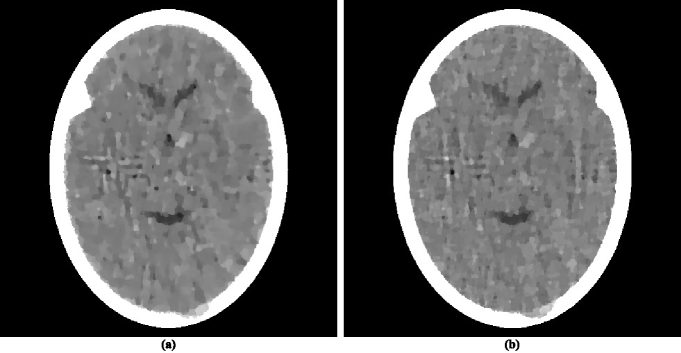

There have appeared in the literature some approaches to minimization that seem to indicate a more efficacious performance for CT than the one reported in HERM08a (31). One of these is the Adaptive Steepest Descent Projections Onto Convex Sets (ASD-POCS) algorithm, which is described in detail in the much-cited paper of Sidky and PanSIDK08a (42) and whose use has been since reported in a number of subsequent publications, for example, in SIDK11a (23, 43). We note that ASD-POCS was designed with the aim of producing an exact minimization algorithm, in contrast to our heuristic superiorization approach. Translating equations (6)-(8) of SIDK08a (42) into our terminology, the aim of ASD-POCS is the following: Given an , find an -compatible for which is minimal. (Note that this aim is a special case of the constrained optimization formulation presented in (10).) In order to test ASD-POCS, we generated realistic projection data as described in the previous subsection but for only 60 views at 3 degree increments with the spacing between the lines for which integrals are estimated set at 0.752 mm. Thus the number of rays (and hence the number photons put into the head) in this data set is a twelfth of what it is in the data set used to produce the reconstruction in figure 1(b). A reconstruction from these data was produced for us using ASD-POCS by the authors of SIDK08a (42) (this ensured that it does not suffer due to our misinterpretation of the algorithm or from our inappropriate choices of the free parameters), it is shown in figure 2(a).

While this ASD-POCS reconstruction is not as good as it should be for diagnostic CT of the brain (due to the sparsity of the data), it is visually better than the reconstruction using superiorization from similar data as reported inHERM08a (31). We discuss the reasons for this in the next subsection. Here we concentrate on examining whether one can achieve a reconstruction using superiorization that is as good as that produced by ASD-POCS from the same data.

For this we first need to examine the numerical properties of the ASD-POCS reconstruction. This reconstruction uses pixels each of size 0.376 mm by 0.376 mm. This implies that and it also determines the components of the vectors in the precise specification of the problem . The , as defined by (2), of the ASD-POCS reconstruction is 0.33 and the , as defined by (12), is 835.

We applied to the same problem a superiorized version of the algorithm defined by (3). To complete the specification of , we point out that for the ordering of views we chose the “efficient” one that was introduced in HERM93a (58) and is also discussed on page 209 of HERM09a (55). The choices we made for the superiorization are the following: , is the zero vector and . The nonascending vector was computed by the method described in the paragraph below (12). Denoting by the infinite sequence of points in that is produced by the superiorized version of the algorithm when applied to the problem , we chose as our reconstruction . For such a reconstruction we have, by the definition of , that ; in other words, the output of the superiorization algorithm is at least as constraints-compatible with as the output of ASD-POCS. From the point of view of -minimization, our is slightly better: 826.

The superiorization reconstruction is displayed in figure 2(b). Visually it is similar to the reconstruction produced by ASD-POCS. From the optimization point of view it achieves the desired aim better than ASD-POCS does, since it results in smaller values for both and for , even though only slightly.

That the two reconstructions in figure 2 are very similar is not surprising because a comparison of the pseudo-codes reveals that the ASD-POCS algorithm in SIDK08a (42) is essentially a special case of the Superiorized Version of Algorithm , even though it has been derived from rather different principles. To obtain the ASD-POCS algorithm from our methodology described here, we would have to choose an Algebraic Reconstruction Technique (ART; see Chapter 11 of HERM09a (55)) as the algorithm that we are superiorizing. Such a superiorization of ART was reported in the earliest paper on superiorization BUTN07a (27). For the illustration in our current paper we decided to superiorize the block-iterative algorithm defined by (3). This illustrates the generality of the superiorization approach: it is applicable not only to a large class of constrained optimization problems, but also enables the use of any of a large class of iterative algorithms designed to produce a constraints-compatible solutions. A recent publication aimed at producing an exact -minimizing algorithm based on the block-iterative approach is DEFR11a (44).